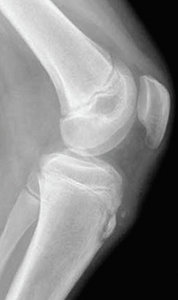

While we don't have the space to review all the high-risk overuse injuries, there are a few quite common ones I'd like to mention. One of the more common sports-related injuries is Osgood-Schlatter disease, which is actually a misnomer because it is not a disease. The condition is a result of a traction apophysitis at the tibial tuberosity due to the pull of the quadriceps muscle group via the patella tendon. Symptoms correlate with the times of rapid growth, typically from ages 12-15 in boys and ages 8 to 15 in girls.

Patients typically complain of insidious onset of anterior knee pain associated with localized swelling at the tibial tuberosity. However, pain also can be initiated by a traumatic event such as a forceful jump, or direct trauma from a fall or blow to the tibial tuberosity.

Pain is exacerbated by activities such as running or jumping. Even kneeling can exacerbate the pain when the apophysis is inflamed. X-rays are helpful primarily to rule out tibial stress fractures.9-10 (Figure 1)